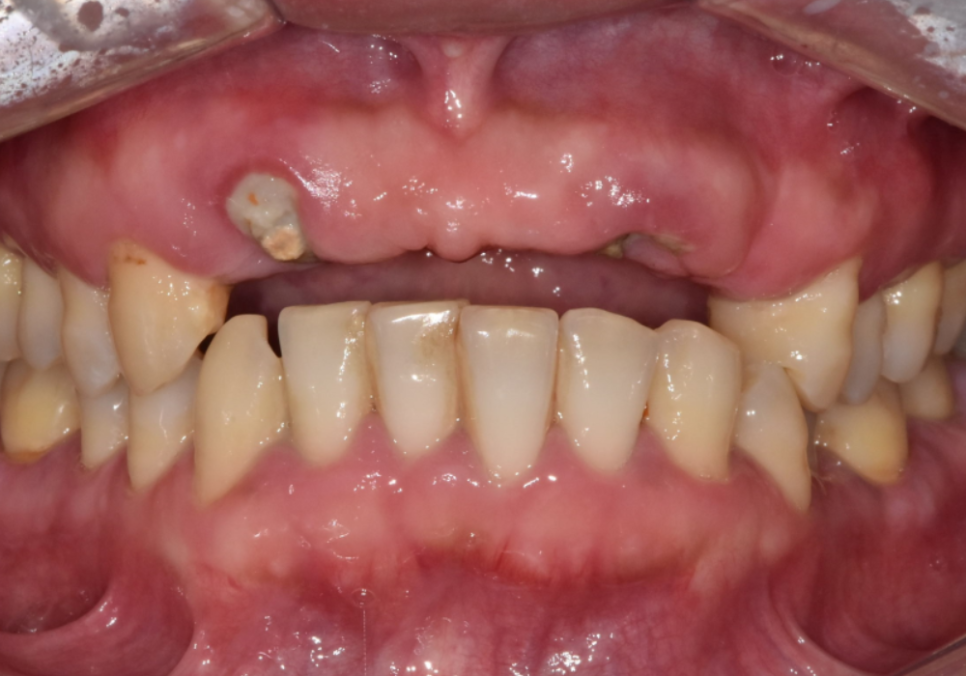

얼마 전 저희 치과를 찾으신 환자분의 사례예요.

3년 전에 타 병원에서 진행한 앞니 브릿지가

통째로 부러져서 저희 치과를 찾아주셨는데요~

입안을 살펴보니 ...

브릿지를 지탱하던 치아 2개(#12, #22)가

잇몸 안에서 완전히 부러져

뿌리만 간신히 남아있는 상태였습니다.